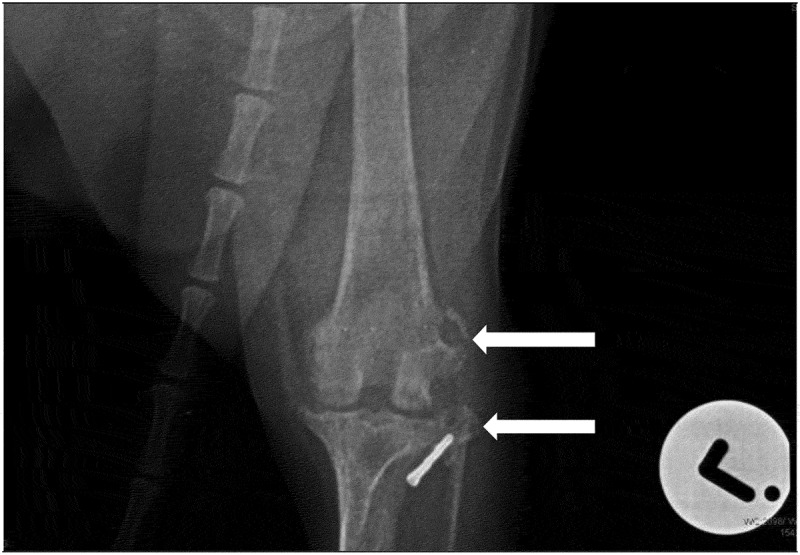

我们描述了一例慢性淋巴浆细胞性绒毛结节性滑膜炎(CLPVNS)与颅十字韧带(CCL)疾病相关的10岁绝育杰克罗素梗母狗。这只母狗被送到兽医诊所,患有严重的、非负重的、急性左后肢跛行。这只母狗先前曾使用外侧腓骨缝合(LFS)技术对同一关节的膝关节CCL疾病进行手术治疗。自治疗以来,患者有间歇性左后肢非负重性跛行史,可通过非甾体抗炎药(NSAIDs)治疗。触诊和操作受影响的膝关节引起剧烈疼痛。没有其他临床或矫形异常。受影响的膝关节的正交x线片显示中度退行性关节疾病和股骨外侧髁外侧和腓骨头部的溶骨性病变。从关节处抽吸的液体培养细菌生长阴性。细胞学结果怀疑为CLPVNS。探查性关节切开术、滑膜切除术、清创术及关节灌洗术。获得关节的骨和滑膜活检样本并提交实验室进行组织病理学确诊。细胞学初步诊断CLPVNS,活检标本病理证实。本病例报告强调了在伴有CCL疾病的跛行犬中检查CLPVNS的重要性,因为报告显示它被低估或误诊。

We describe a case of chronic lymphoplasmacytic villonodular synovitis (CLPVNS) associated with cranial cruciate ligament (CCL) disease in a 10-year-old spayed Jack Russell Terrier bitch. The bitch was presented to a veterinary clinic with severe, non-weight bearing, acute left hindlimb lameness. The bitch had previously been treated surgically for stifle CCL disease of the same joint, using the lateral fabellar suture (LFS) technique. Since the treatment, the patient had a history of intermittent left hindlimb non-weight bearing lameness that was manageable with nonsteroidal anti-inflammatory drugs (NSAIDs). Palpation and manipulation of the affected stifle elicited severe pain. There were no other clinical or orthopaedic abnormalities. Orthogonal radiographs of the affected stifle revealed moderate degenerative joint disease and osteolytic lesions on the lateral aspect of the lateral femoral condyle and the head of the fibula. A fluid aspirate from this joint was negative for bacterial growth on culture. Cytology results were suspicious for CLPVNS. Exploratory arthrotomy, synovectomy, debridement and lavage of the affected joint were performed. Bone and synovial membrane biopsy samples of the joint were obtained and submitted to a laboratory for a histopathological confirmatory diagnosis. CLPVNS was tentatively diagnosed by cytology, and confirmed by histopathology of biopsy samples. This case report highlights the importance of checking for CLPVNS in dogs with lameness associated with CCL disease, as reports show it to be underreported or misdiagnosed.